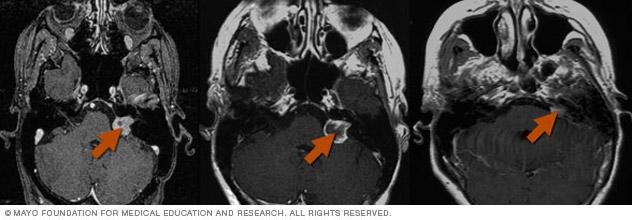

Scans of a brain tumor before and after treatment.

Brain tumor before and after Gamma Knife treatment

Malignant brain tumor before (left) and 111 months after Gamma Knife stereotactic radiosurgery (right)